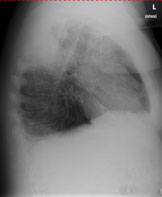

Einer Ihrer Patienten wird wegen einer Pneumonie seit 10 Tagen antibiotisch behandelt. Sie veranlassen eine Thoraxröntgen zur Verlaufskontrolle.

Hier sehen Sie das Kontrollröntgen:

Thorax seitlich

Bild vergrössern

Wie beurteilen Sie das aktuelle Thoraxröntgen (mehrere richtige Antworten möglich):